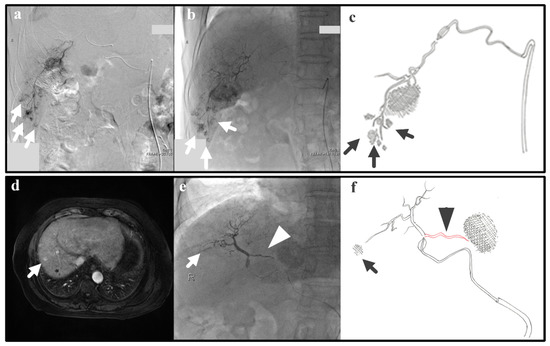

In real clinical cases, arterial hemodynamics is complex due to varied and not-always-visible collateral pathways. Thus, we examine real cases that are relevant to the IVM testing; despite the simplicity of the IVM, the successfulness/unsuccessfulness of clinical cases can also be explained with the IVM. The following two clinical cases represent Experiments 1 and 2, which give as a result efficient and inefficient B-TACE procedures, respectively. Experiment 1 (i.e., a single tumor and successful B-TACE) is similar to the case of a patient (patient 1) with previous embolization of a 3-cm tumor in S6 that underwent B-TACE after multiple early stains were detected in angiogram (arrows in Figure 8a). Dense accumulation of lipiodol with miriplatin was shown during B-TACE (arrow in Figure 8b,c).

Experiment 2 (i.e., a single tumor and unsuccessful B-TACE) is similar to the case of a patient (patient 2) that underwent B-TACE after an early 1-cm tumor at S8 (i.e., the therapeutic target) was detected with MRI (Figure 8d). During embolization of S8, the microballoon tip pressure was above 64 mmHg, suggesting that collateral circulation existed. Indeed, accumulation of lipiodol with miriplatin was not enhanced (arrow in Figure 8e,f) as a pronounced collateral pathway emerged toward S4 (arrowhead in Figure 8e,f). These two clinical cases show that the IVM can reproduce clinically realistic scenarios.

Figure 8. Patient 1: (a) Angiogram for tumor detection, (b) lipiodol accumulation during B-TACE, (c) a hand drawing showing the tumors, the hepatic artery, and the microballoon catheter. Patient 2: (d) MRI for tumor detection and (e) no lipiodol accumulation in the tumor (arrow), collateral pathway promotion (arrowhead) during B-TACE, and (f) a hand drawing showing the target tumors, the hepatic artery, the microballoon catheter, and the collateral artery.